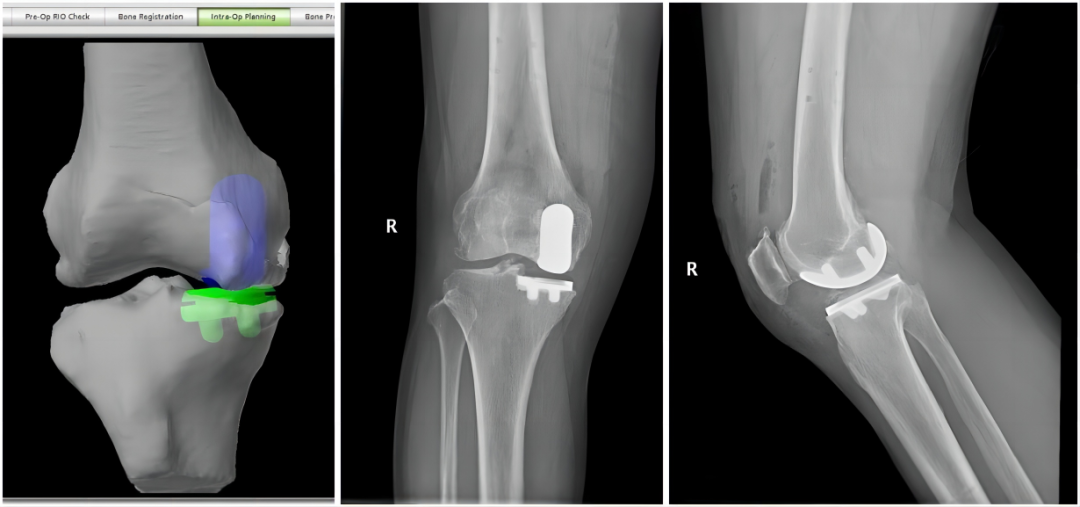

经过手术方案的沟通,康复科医生和治疗师进行了详细的术前评估,量身定做术后康复方案,并对康复训练进行了必要的预习等,一系列的术前准备就绪后,陈女士在MAKO机器人辅助下,完成单髁置换术。

MAKO手术机器人辅助具有术前量身定制的手术方案、术中假体精准植入,误差可以控制在1度和1毫米以内、术后快速康复的优势。而对于单髁置换手术,MAKO机器人的优势更加让人关注。

MAKO机器人辅助单髁置换术所搭配的关节假体是史塞克公司MCK假体,该假体为全解剖型设计,更好的与人体骨骼形态相匹配。传统单髁置换手术已经具有微创、不损伤肌肉、保留骨量多、术后恢复快的优点,从这个病例中,MAKO机器人把这种优势进一步增加,并且更加精准,表现在以下几点:

单髁关节置换术的手术视野有限,与传统手术相比,单靠主治医生肉眼判断容易出现误差。而MAKO机器人可以帮助医生判断截骨的位置,使关节假体放置的位置更加准确,避免假体过大或过小,也可以避免假体周围骨折、软组织激惹等;

通过机器人辅助下的间隙平衡,通过调整假体位置,可以获得膝关节全活动范围内的软组织平衡;

股骨假体设计为解剖型,不容易刺激髌骨。基于以上技术优势,MAKO机器人手术患者与传统手术相比,术后短期内的疼痛更轻,恢复更快,更容易忘记关节做了手术,满意度更高(超过90%),而远期假体生存率更高(可达97%)。